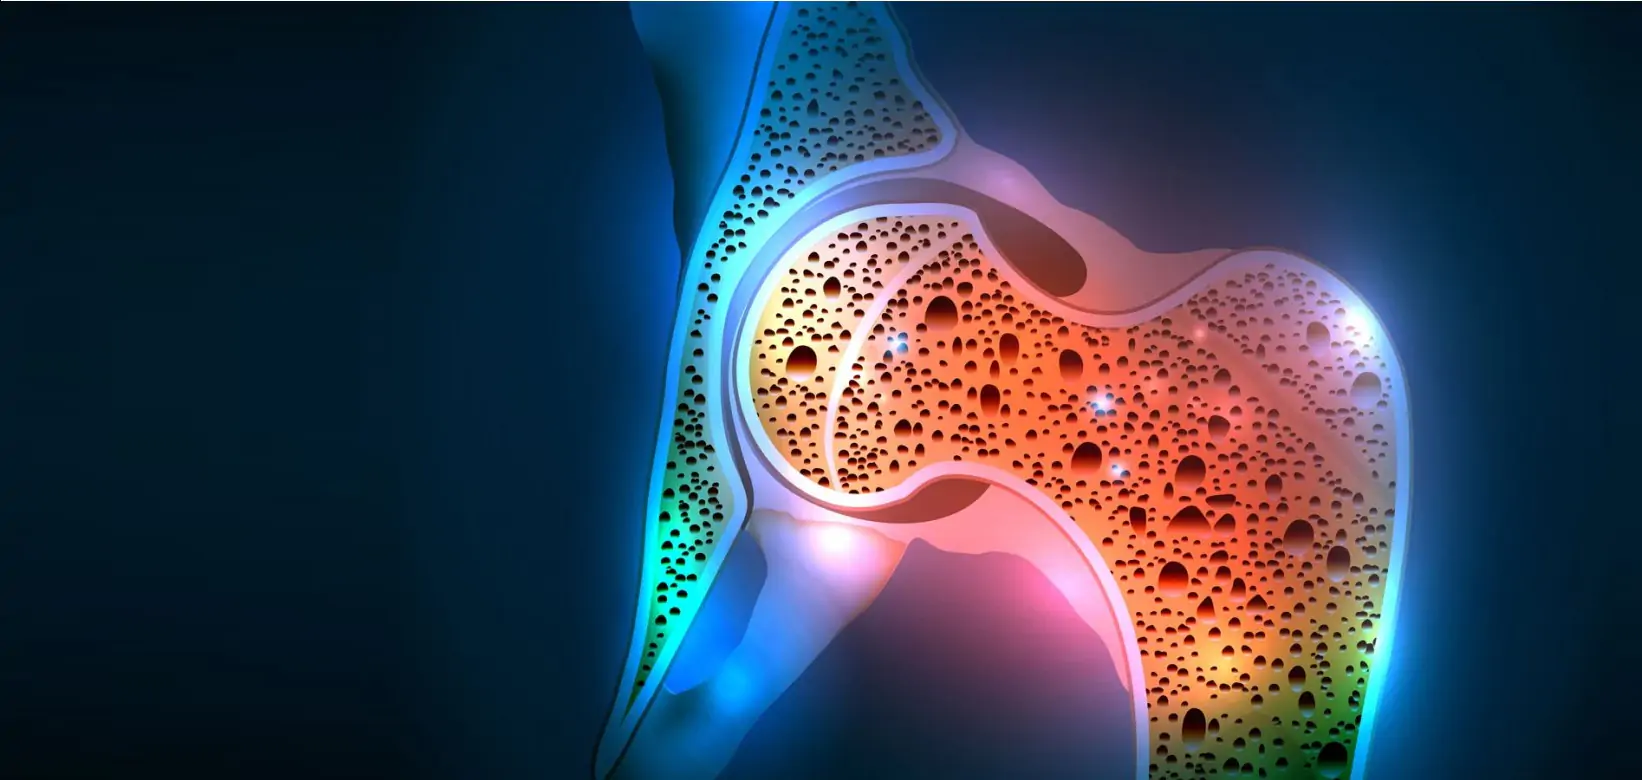

Иллюстрации и снимки, связанные с остеопенией шейки бедра